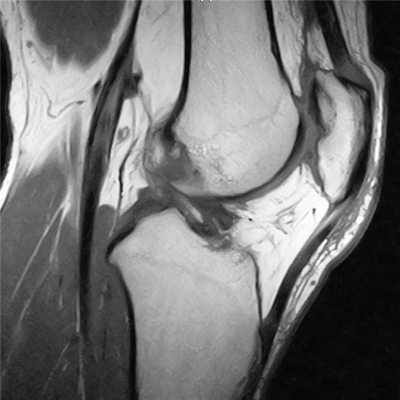

МРТ коленного сустава показывает наличие кисты Бейкера в подколенной ямке (обозначена стрелкой)

Возможно ее обратное развитие вплоть до полного исчезновения, но при условии своевременной диагностики и лечения. При длительном её существовании содержимое кисты затвердевает, формируется спаечный процесс. Возможен ее разрыв, приводящий к появлению острых болей, отеку в подколенной ямке и области голени. В таком случае особое значение приобретает МРТ, которая дает возможность провести дифдиагностику с другими патологиями.